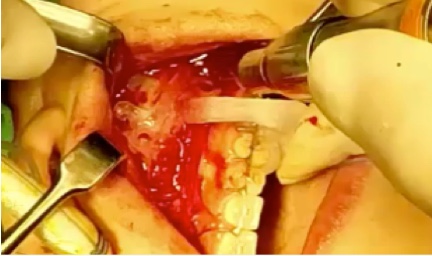

FACEGIDE™

Customized orthognathic solutions

Saw Guides

- Customized for each patient to ensure precise bone incisions & deletions

Facial Reconstruction Surgery

Customized facial reconstruction solutions